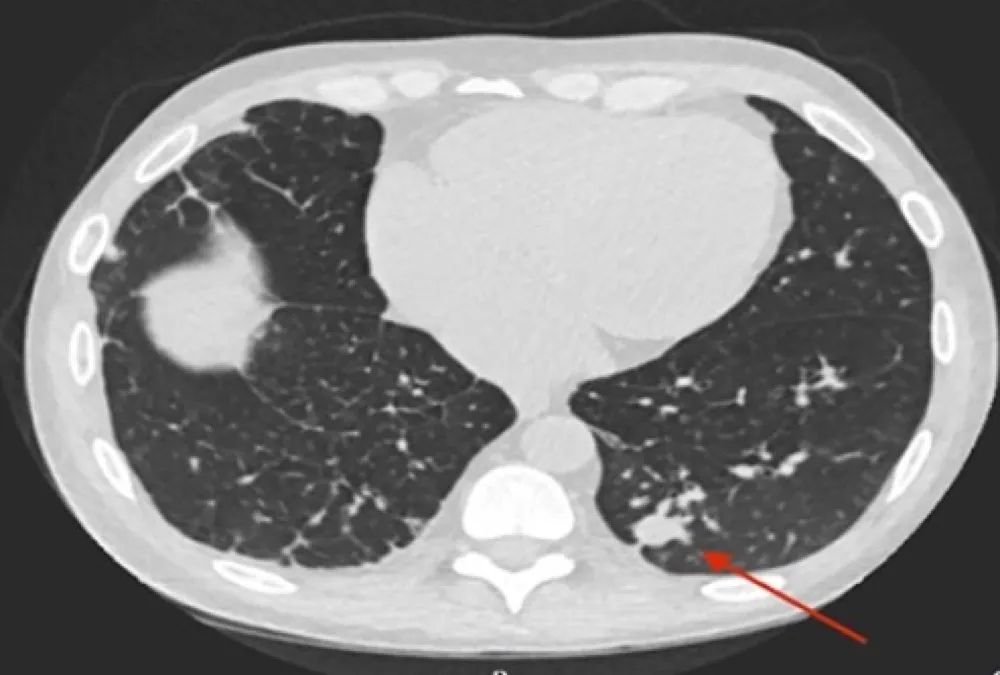

DRC indeterminada ou você esqueceu de fazer o básico? Veja tudo aqui

DRC “indeterminada” raramente é falta de diagnóstico — quase sempre é falta de método. Tempo de evolução, urina bem avaliada, USG renal e história clínica dirigida mudam conduta e evitam erros comuns na prática nefrológica.